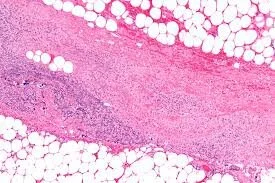

Necrotizing fasciitis is an uncommon, severe infection involving the subcutaneous soft tissues including the superficial fascia. Historically, it has been divided into two types with Type I involving anaerobic flora and Type II involving Streptococcus pyogenes (group A Strep or GAS)—often referred to as “flesh eating bacteria.” Type II can also be associated with other bacteria including staphylococci. The portal of bacterial entry is usually a site of trauma or injury. The most common site of involvement is an extremity. Early differentiation from cellulitis, a less severe skin infection, can be difficult.

A patient with necrotizing fasciitis can present with swelling and induration with some erythema but usually not with defined sharp margins. The area is exquisitely tender. The skin of the infected area can progress rapidly over several days and develop purple or gray discoloration. Over time, pain may be replaced by anesthesia of the infected area.

The treatment of necrotizing fasciitis is surgical debridement. In most cases, a large amount of necrotic tissue is removed, commonly parts or entire limbs. Broad-spectrum antibiotics alone are not curative.